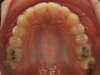

L'encombrement chez l'adolescent

Manque de place :

(encombrement - dysharmonie dento-maxillaire)